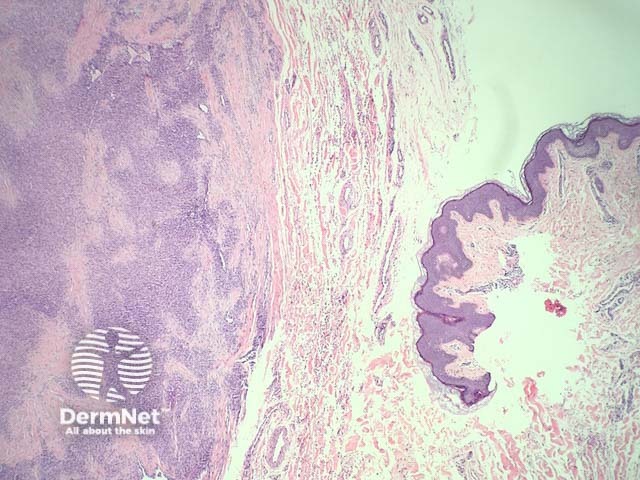

The histopathology in synovial sarcoma may be biphasic (consisting of spindled and epithelioid cells), monophasic (only spindled cells), or undifferentiated (difficult to recognise without cytogenetic tests). These tumours are usually present in the deep soft tissues but occasionally they are seen in the dermis (figure 1). The spindle cells are arranged in plump fascicles with hyalinization and distinct lobulation (figures 2,3) Biphasic tumours have spindle cells resembling synoviocytes and plump epithelial cells forming glands/cords (figure 4, the epithelioid component is indicated with the arrow).

Figure 1